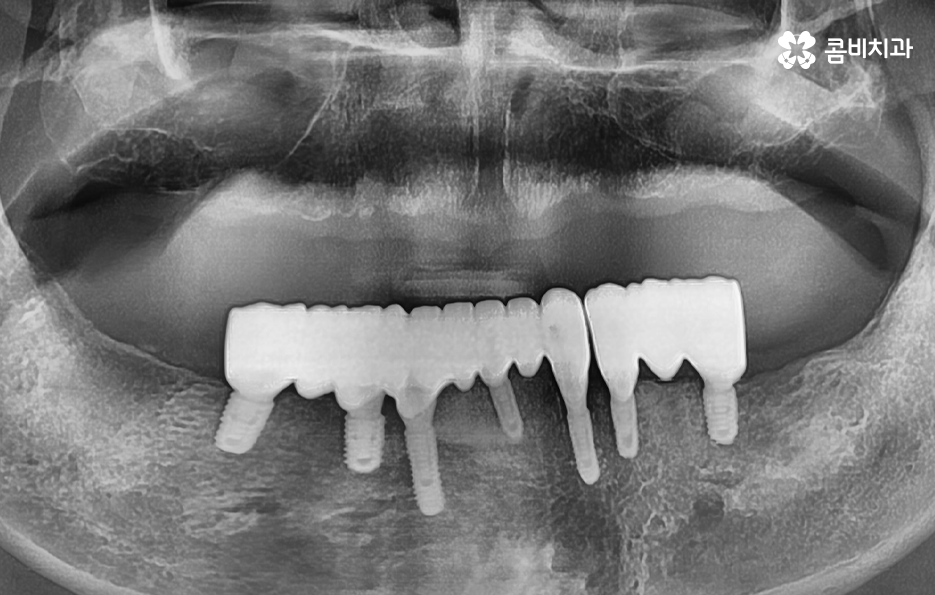

임플란트 브릿지를 활용하여 전체임플란트를 하는 경우 보통 임플란트를 6~8개 정도 식립을 한 후에 임플란트의 머리부분을 연결하여 힘을 분산시키는 방법으로 저작력을 유지시키고 있어요

치아는 각 치아마다의 고유의 기능을 갖고 있고 전체적으로 본다면 앞니는 보통 음식물을 자르고 어금니는 주로 음식을 씹는 역할을 하는 것처럼 부위마다의 역할도 갖고 있는데요.

임플란트 브릿지를 활용하여 전체임플란트 하는 경우에는 환자분의 잇몸 상태에 따라서 다르게 치료 방법이 진행되긴 하겠으나 통상적으로는 치아 역할의 파트 별로 구분하여 보철물을 연결하고 있어요